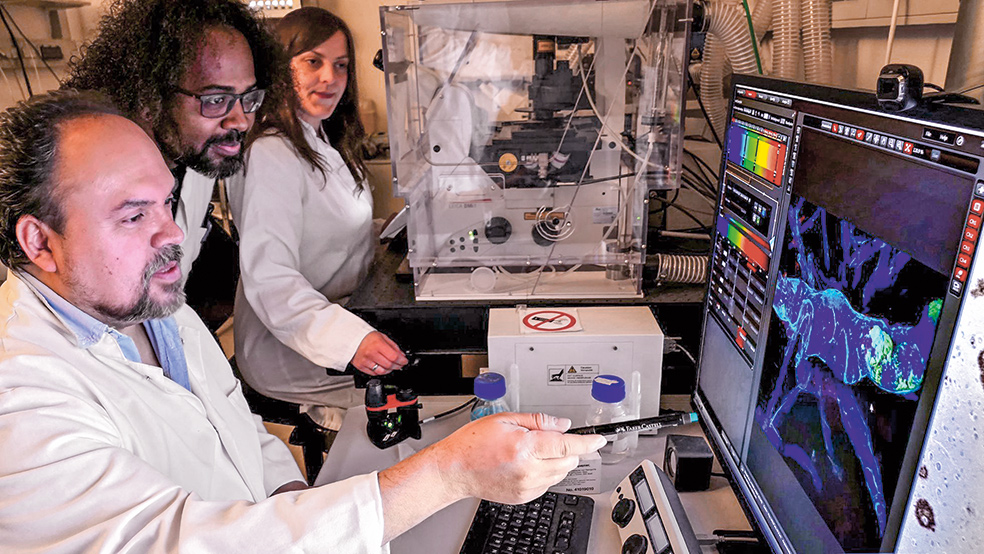

Una nube de vapor envuelve a Diego Sepúlveda cuando abre el congelador de su laboratorio. Tiene que darse prisa en coger el envase correcto. La temperatura no debe subir de los 76 grados bajo cero. El material que guarda el arcón es valioso y delicado: el tejido cerebral de 100 personas. Uno de los tubos contiene una masa grisácea del tamaño de una almendra y pertenece a un sujeto a quien este neuropatólogo que trabaja en Hamburgo lleva tiempo estudiando. Se trata de un hombre de Medellín (Colombia) que murió por una inflamación pulmonar. Pero lo más importante: llegó a los 74 años.

El doctor Sepúlveda, junto con médicos de Medellín y de la Universidad de Harvard, acaba de publicar los resultados de sus estudios en la revista Nature Medicine. Los autores han hallado en el ADN del paciente una especie de antídoto natural contra el alzhéimer, un ángel de la guarda genético que protegió su cerebro de un deterioro precoz y devastador.

De todos modos, eso no impidió que el cerebro del hombre presentara un aspecto terrible, habitual en los enfermos de alzhéimer: por todas partes había depósitos proteicos en forma de placas y fibrillas. También había evidencias de una mortandad neuronal masiva. «Pocas veces había visto una atrofia tan severa», dice Sepúlveda. Sin embargo, descubrió que esa muerte de neuronas no había alcanzado a una región concreta. La corteza entorrinal parecía intacta. «Esta región tiene un papel central en la enfermedad», concluye.

Tras numerosos estudios, el neuropatólogo y sus colegas de Harvard y Medellín consiguieron identificar en el ADN de la colombiana un mecanismo protector: en su caso, el gen de 'la bobera' tenía una variante muy especial en la proteína apoE. Por otro lado, Lopera localizó a otra persona que, a pesar de portar el gen, parecía inmune a los síntomas de 'la bobera'. Esta vez, era un hombre. Se trata del protagonista del estudio que recientemente han publicado Diego Sepúlveda y sus compañeros de investigación.

La variante protectora del gen apoE identificada en el caso de Aliria no aparecía en su material genético. Sin embargo, los investigadores se toparon con otro posible factor protector. Creen que un cambio extraño en un gen que codifica una proteína llamada 'reelina' es la responsable de que este segundo caso consiguiera escapar también a los efectos del alzhéimer. La reelina se une a los mismos receptores que la apoE, aunque la interacción de los genes aún no está clara. «Pero las piezas del puzle van encajando», dice Joseph Arboleda, el encargado de los análisis genéticos realizados en Harvard.

Más allá de estos prometedores hallazgos, Sepúlveda se muestra fascinado por un detalle muy llamativo: el efecto protector de la reelina se limita a la corteza entorrinal. «Parece que solo es capaz de preservar de la muerte a las neuronas de esta pequeña región cerebral», dice. Este hecho podría tener una enorme relevancia médica: «Tenemos que concentrar los tratamientos en esta región», afirma. También confía en que les permita seguir adentrándose en los secretos de nuestro cerebro: «Todo apunta a que la corteza entorrinal podría ser un cuadro central de conexiones de nuestro pensamiento».